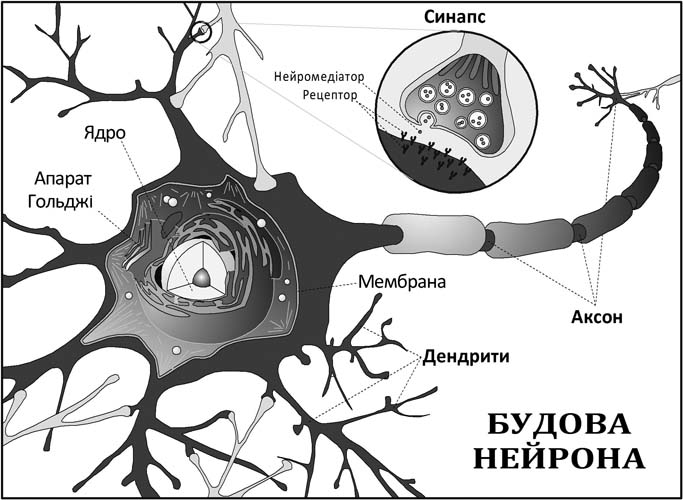

Незважаючи на значний прогрес у дослідженні головного мозку людини, багато чого в його роботі дотепер лишається загадкою. Функціонування окремих клітин добре вивчено й пояснено, проте розуміння того, яким чином у результаті взаємодії десятків мільярдів нейронів мозок функціонує як одне ціле, доступне лиш у сильно спрощеному вигляді, і вимагає подальших глибоких досліджень.